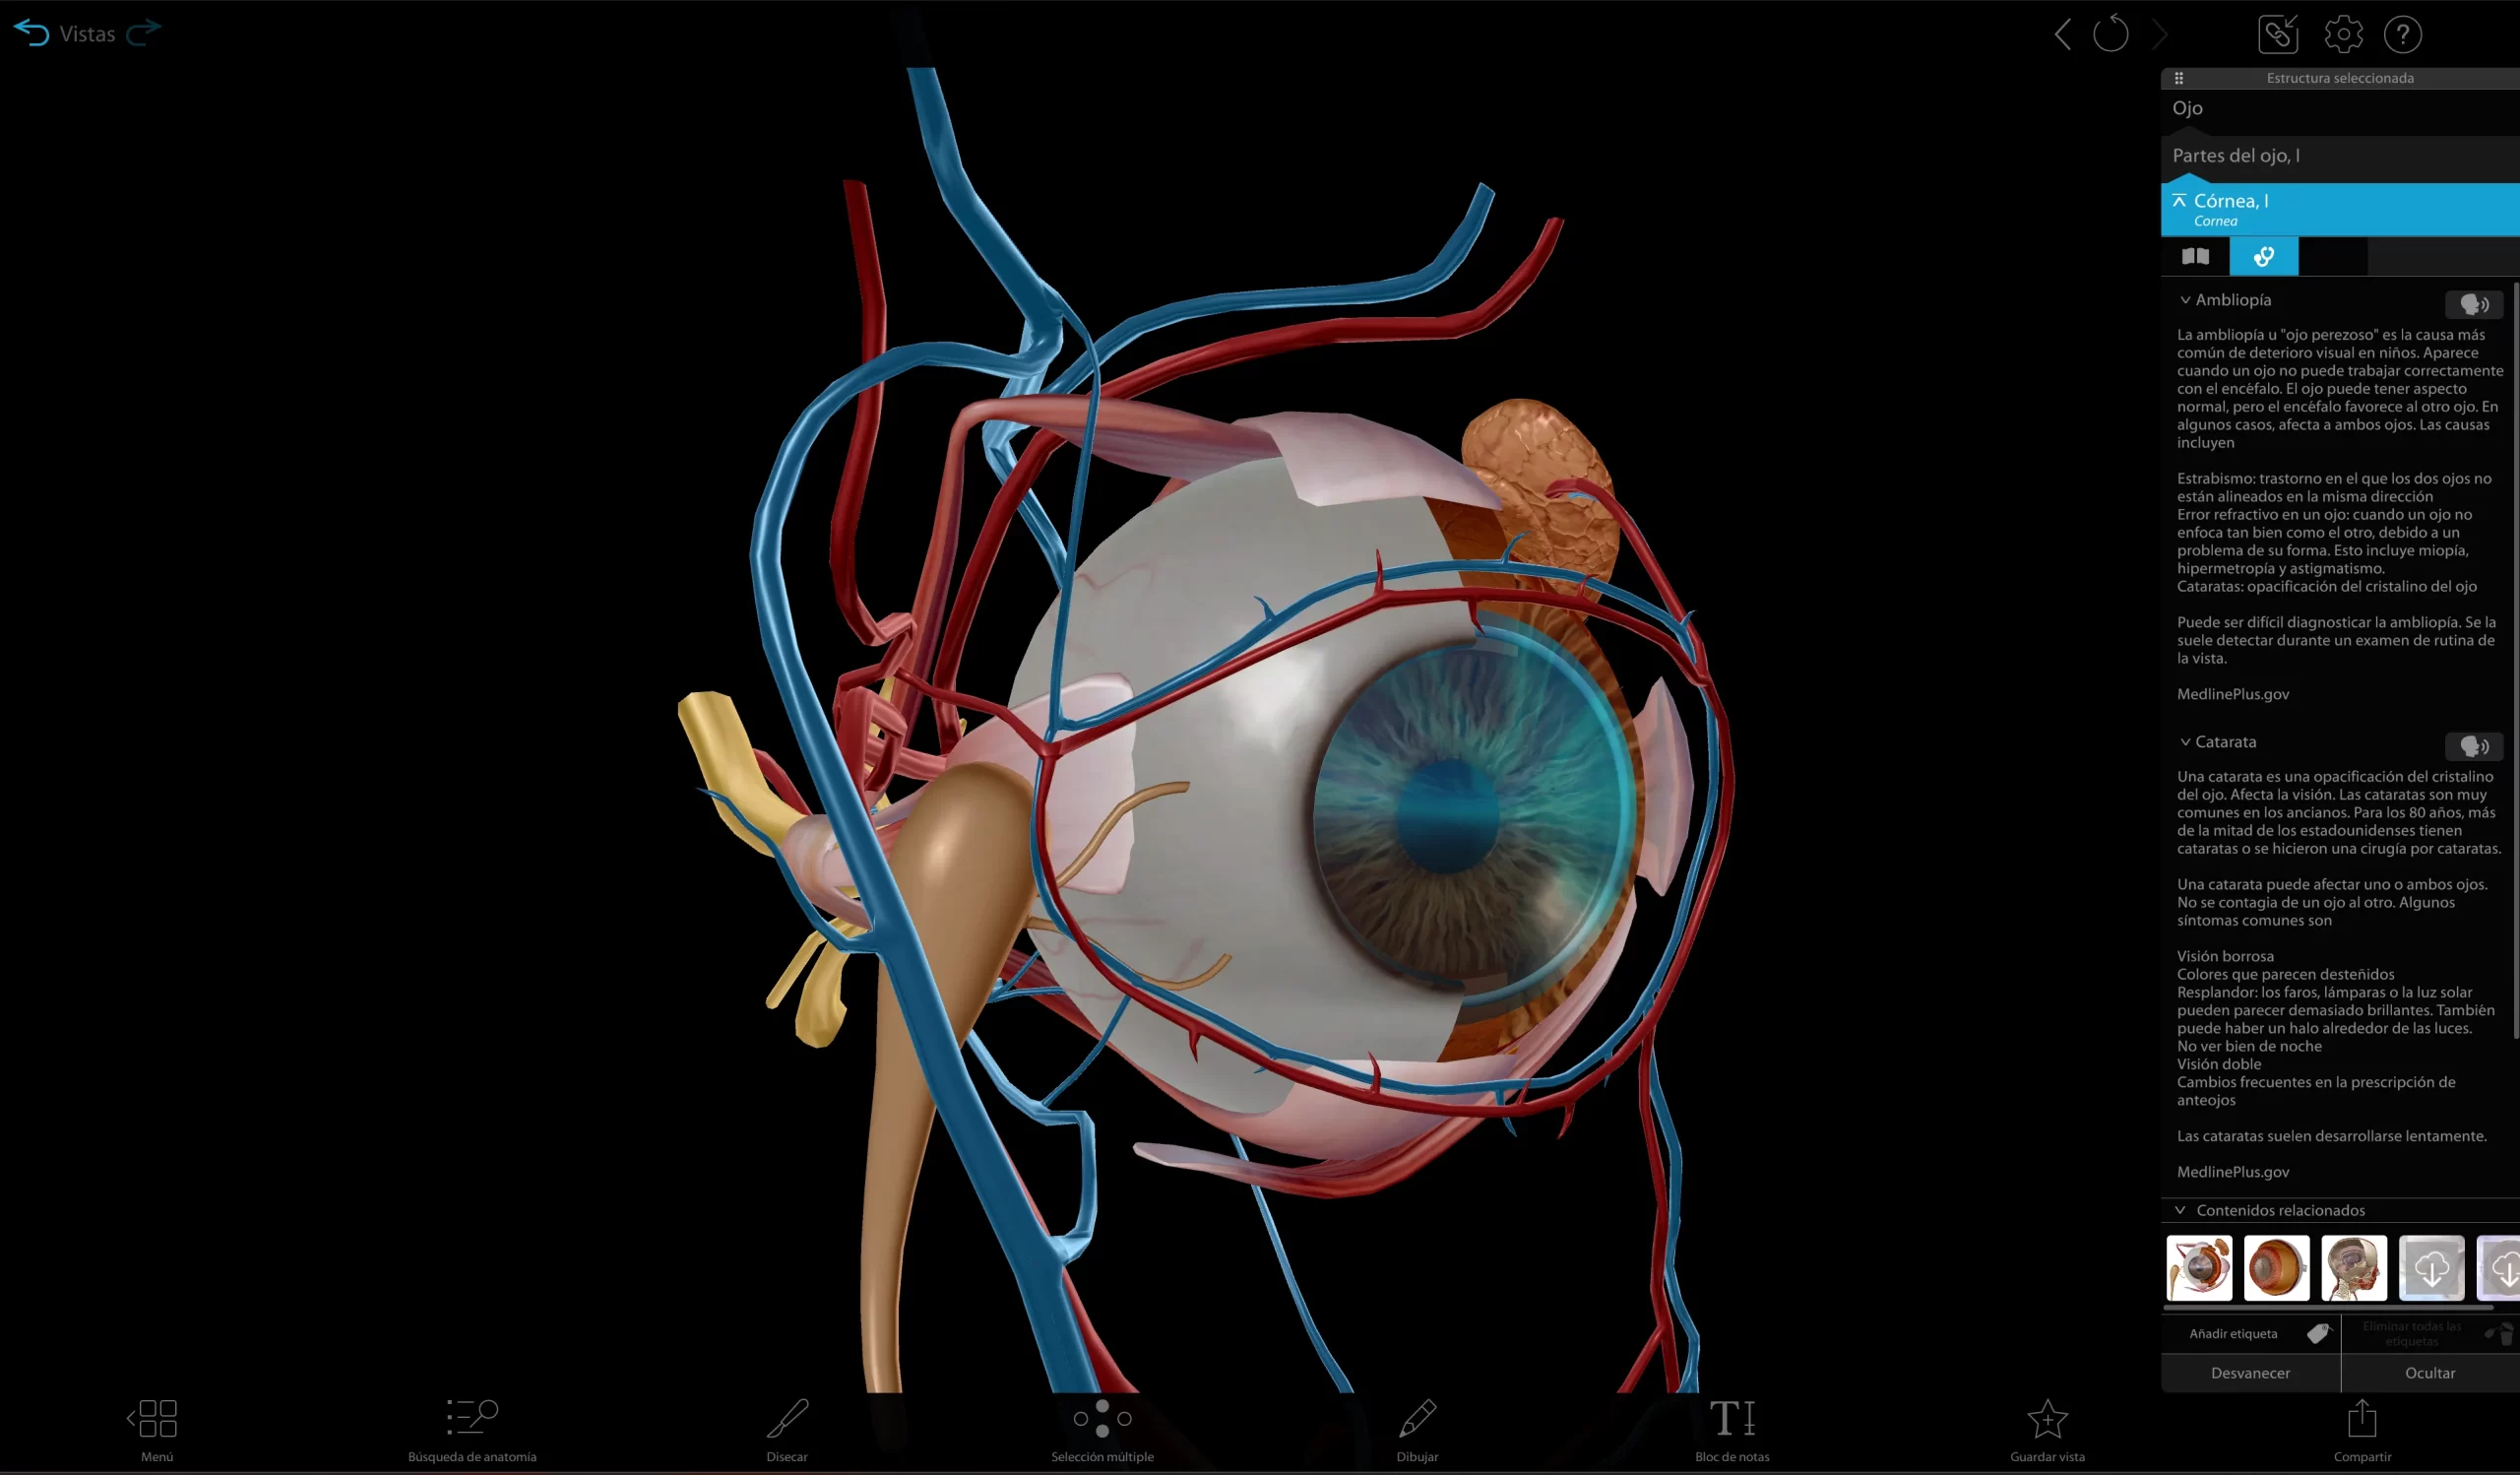

SIT Anatomy

La mesa SIT Anatomy es una solución versátil de alta tecnología con modelos 3D basados en cadáveres reales y renderizados foto realísticamente. Ofrece:

Exploración detallada de la anatomía humana y veterinaria

Herramientas interactivas de disección virtual

Estudio morfofuncional con correlación clínica